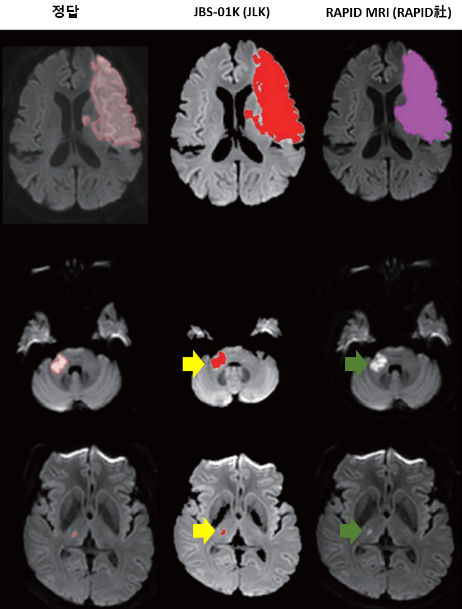

이번 논문에서 연구팀은 허혈성 뇌졸중 영상진단용으로 알려진 제이엘케이의 'JBS-01K'와 미국 RAPID AI사의 'RAPID MRI'를 실제 환자 414명에 적용해 비교 분석했다. 뇌졸중 전문의들이 수작업으로 만든 정답지와 JBS-01K, RAPID MRI의 뇌경색 부피 측정 결과를 검증했다.

그 결과 JBS-01K와 전문의 사이 오차 수준은 RAPID MRI와 전문의 사이 오차 수준의 5분의 1에 불과했다. 특히, RAPID MRI는 제시된 전체 뇌경색 중 39% 환자의 뇌경색만을 검출했지만, JBS-01K는 98.1%의 뇌경색 검출률을 나타내 기술적 성능의 우월성을 나타냈다.